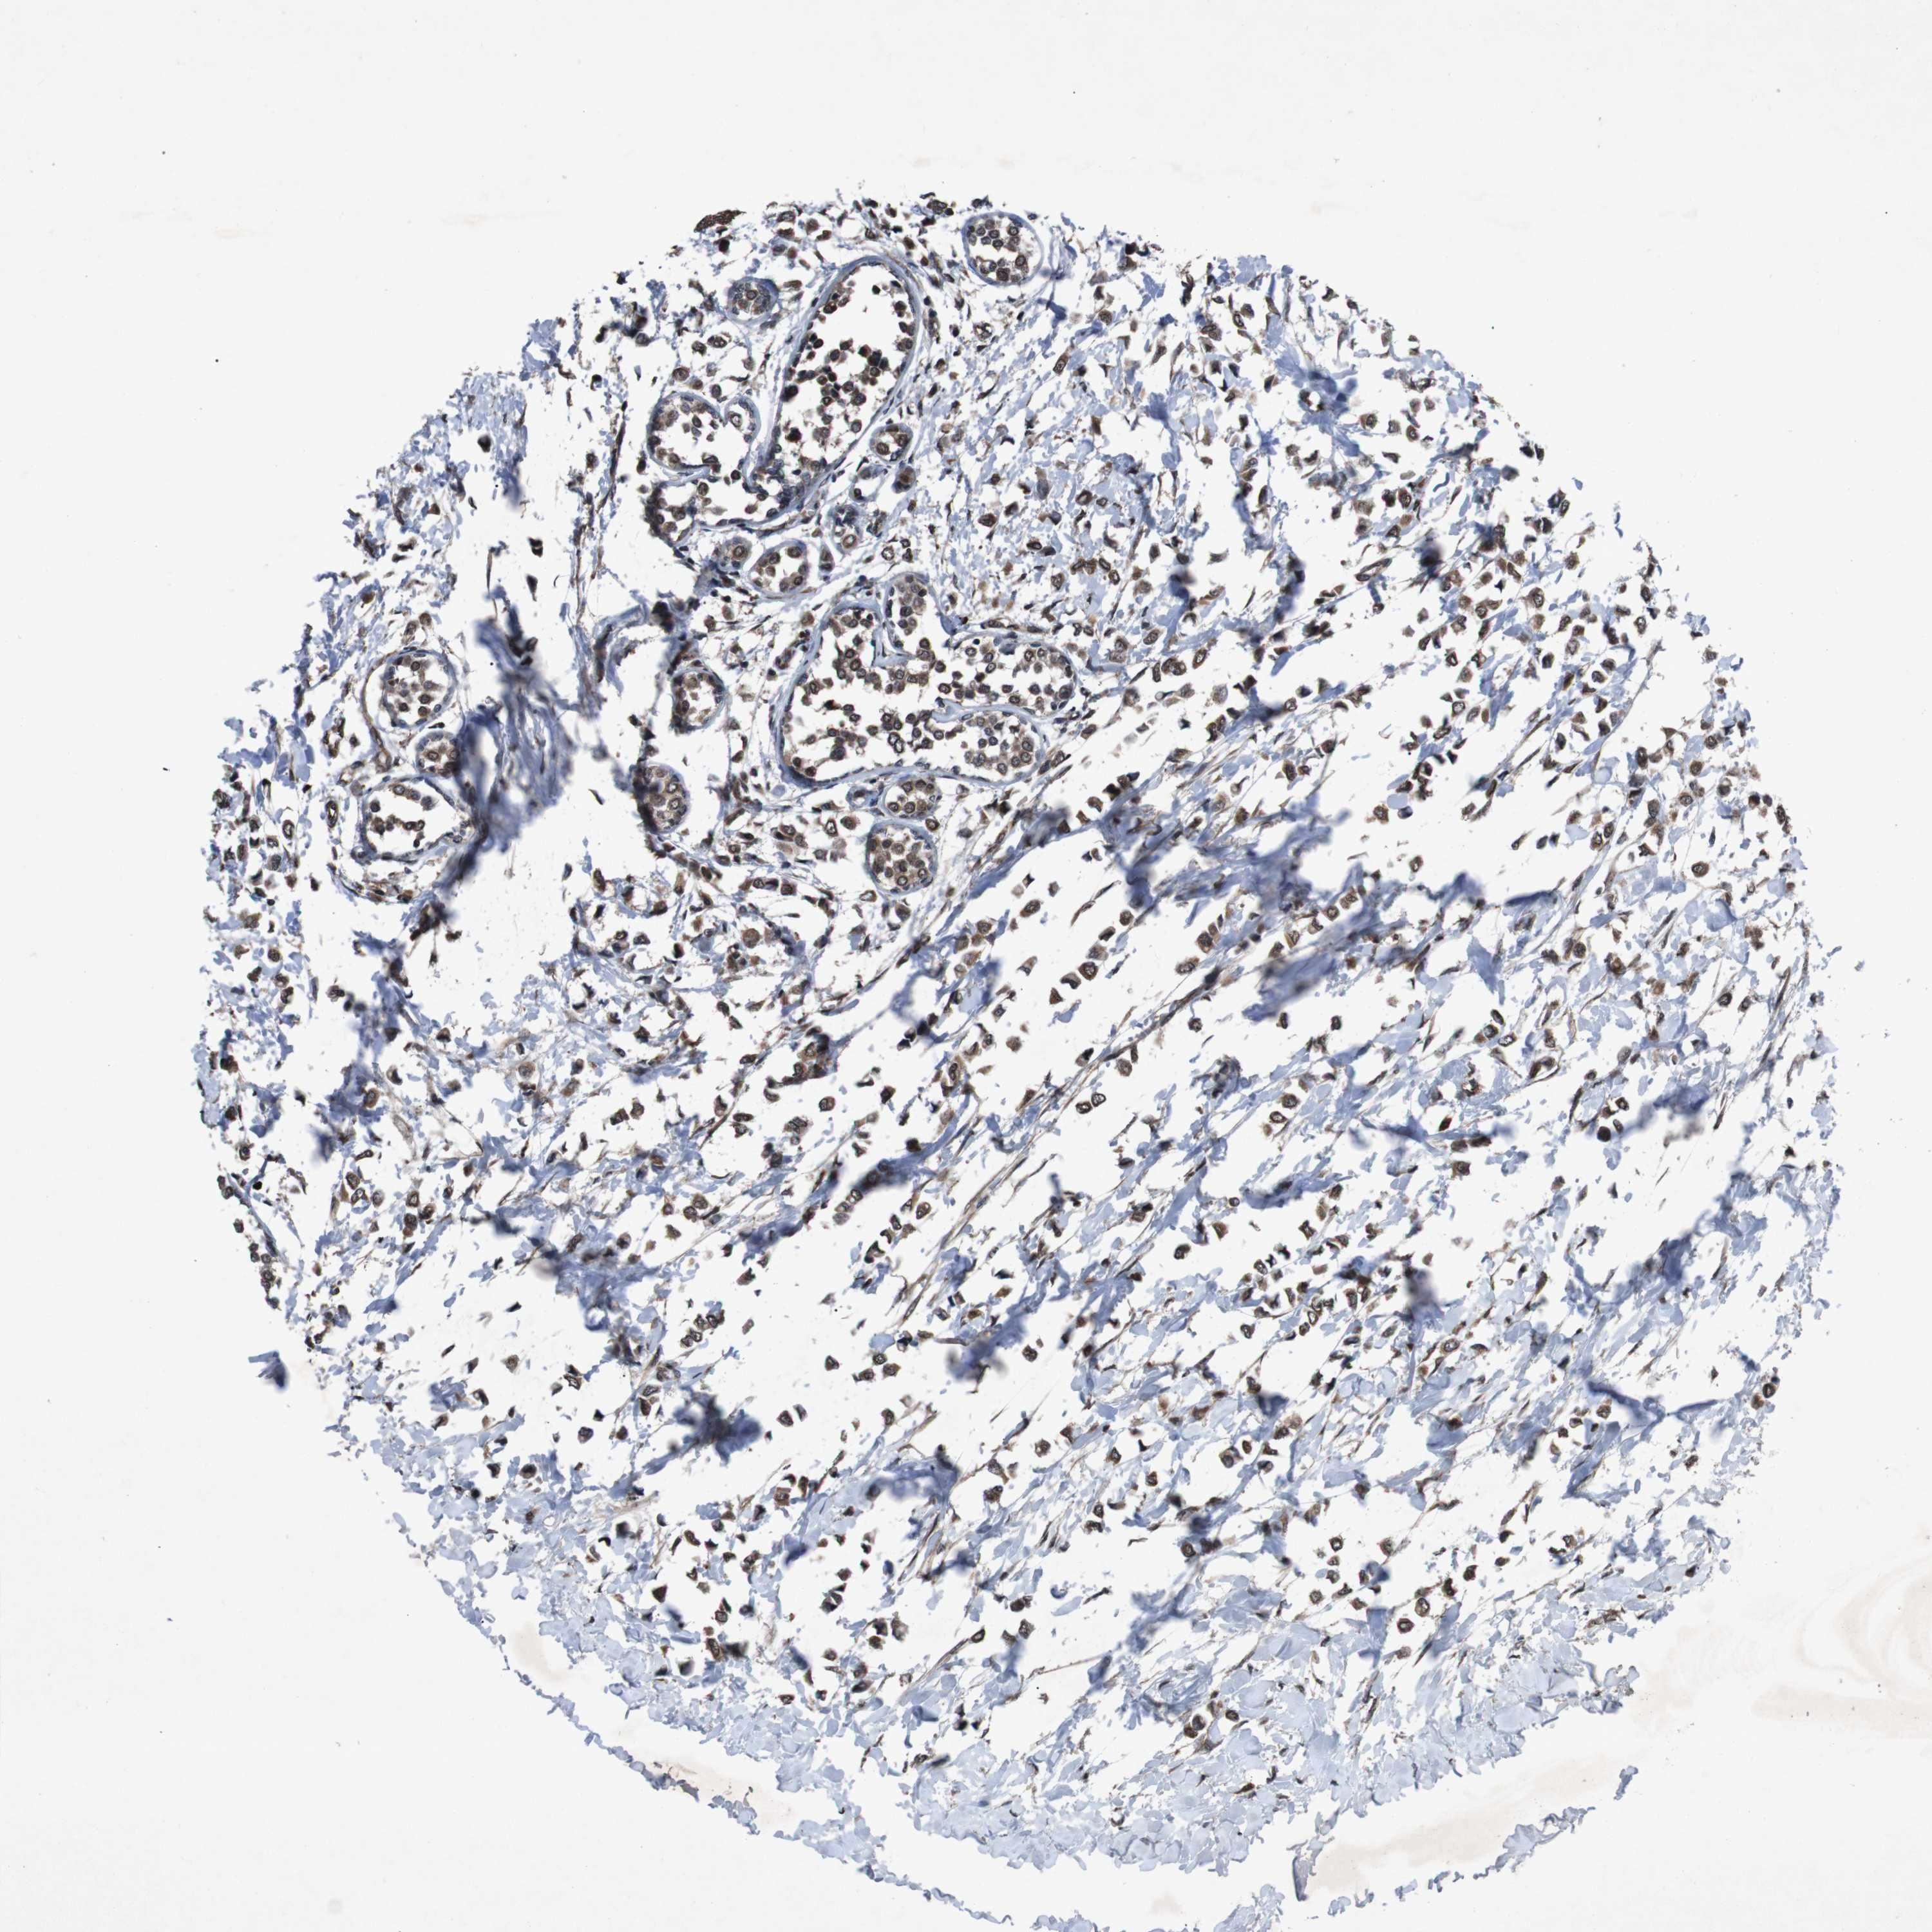

BRCA TCGA BRCA VALIDATION PROTEIN EXPRESSION

ANTIBODIES

AND

VALIDATION